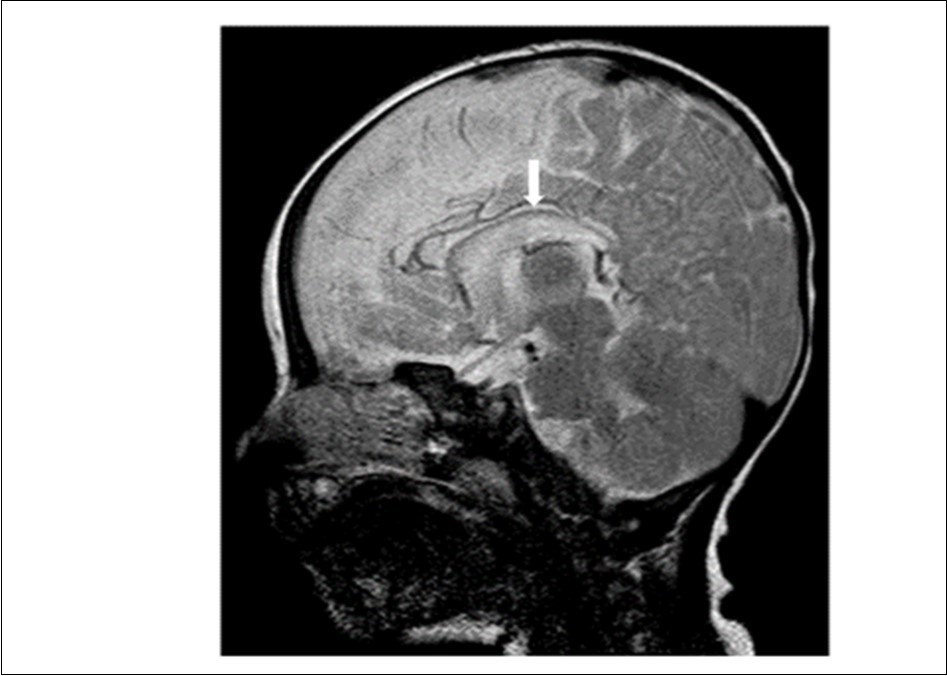

Cranial magnetic resonance imaging (MRI) was requested owing to the patient’s convulsion history and retarded development. The cranial MRI showed diffuse hypoplasia of the corpus callosum in the midline sagittal T2-weighted image (Figure 1 white arrow). T1-weighted imaging showed hypointensity due to delayed myelination of the genu of the corpus callosum (Figure 2, white arrow), which should normally appear hyperintense like the posterior limb of the internal capsule (Figure 2, blue arrow).

Figure 1.Midline sagittal T2-weighted magnetic resonance image of the patient showing diffuse hypoplasia of the corpus callosum.

Midline sagittal T2-weighted magnetic resonance image of the patient showing diffuse hypoplasia of the corpus callosum.